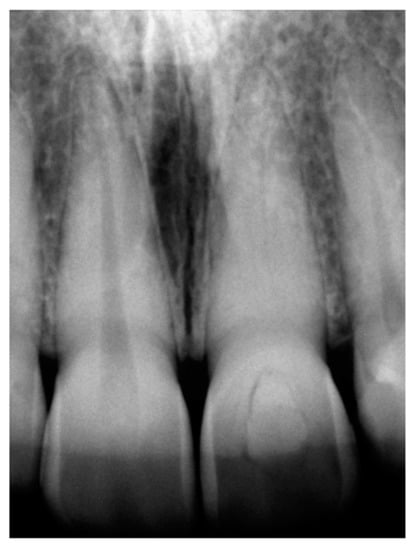

2. Case Presentation